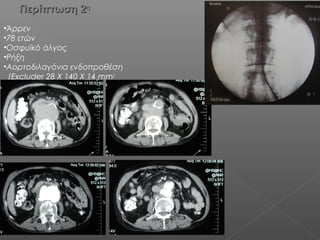

Περίπτωση 2Περίπτωση 2ηη

•Άρρεν

•78 ετών

•Οσφυϊκό άλγος

•Ρήξη

•Αορτοδιλαγόνια ενδοπροθέση

(Excluder 28 Χ 140 Χ 14 mm)